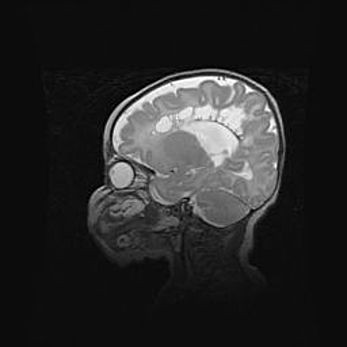

Сообщающаяся гидроцефалия. Кистозная энцефаломаляция головного мозга.

Возраст: 3 месяца 4 дня

Вес: 3100 г

Пол: женский

Окружность головы: 34 см

Срок гестации: 31 неделя

Кистозная энцефаломаляция головного мозга - одна из форм поражения головного мозга в детском возрасте. Характеризуется возникновением множественных и распространённых кист в коре, белом веществе и подкорковых образованиях головного мозга у плодов, новорождённых и детей раннего возраста. Развитие кистозной энцефаломаляции связано с внутриутробной асфиксией и гипотонией, родовой травмой, тромбозом синусов, пороками развития сосудов, инфекциями, сепсисом и другими причинами. Наиболее значимые инфекционные агенты: вирусы простого герпеса, цитомегалии, краснухи, токсоплазмы, энтеробактерии, золотистый стафилококк и другие.